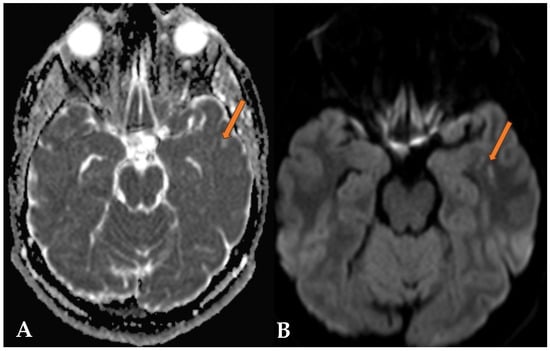

2.2. Case 2